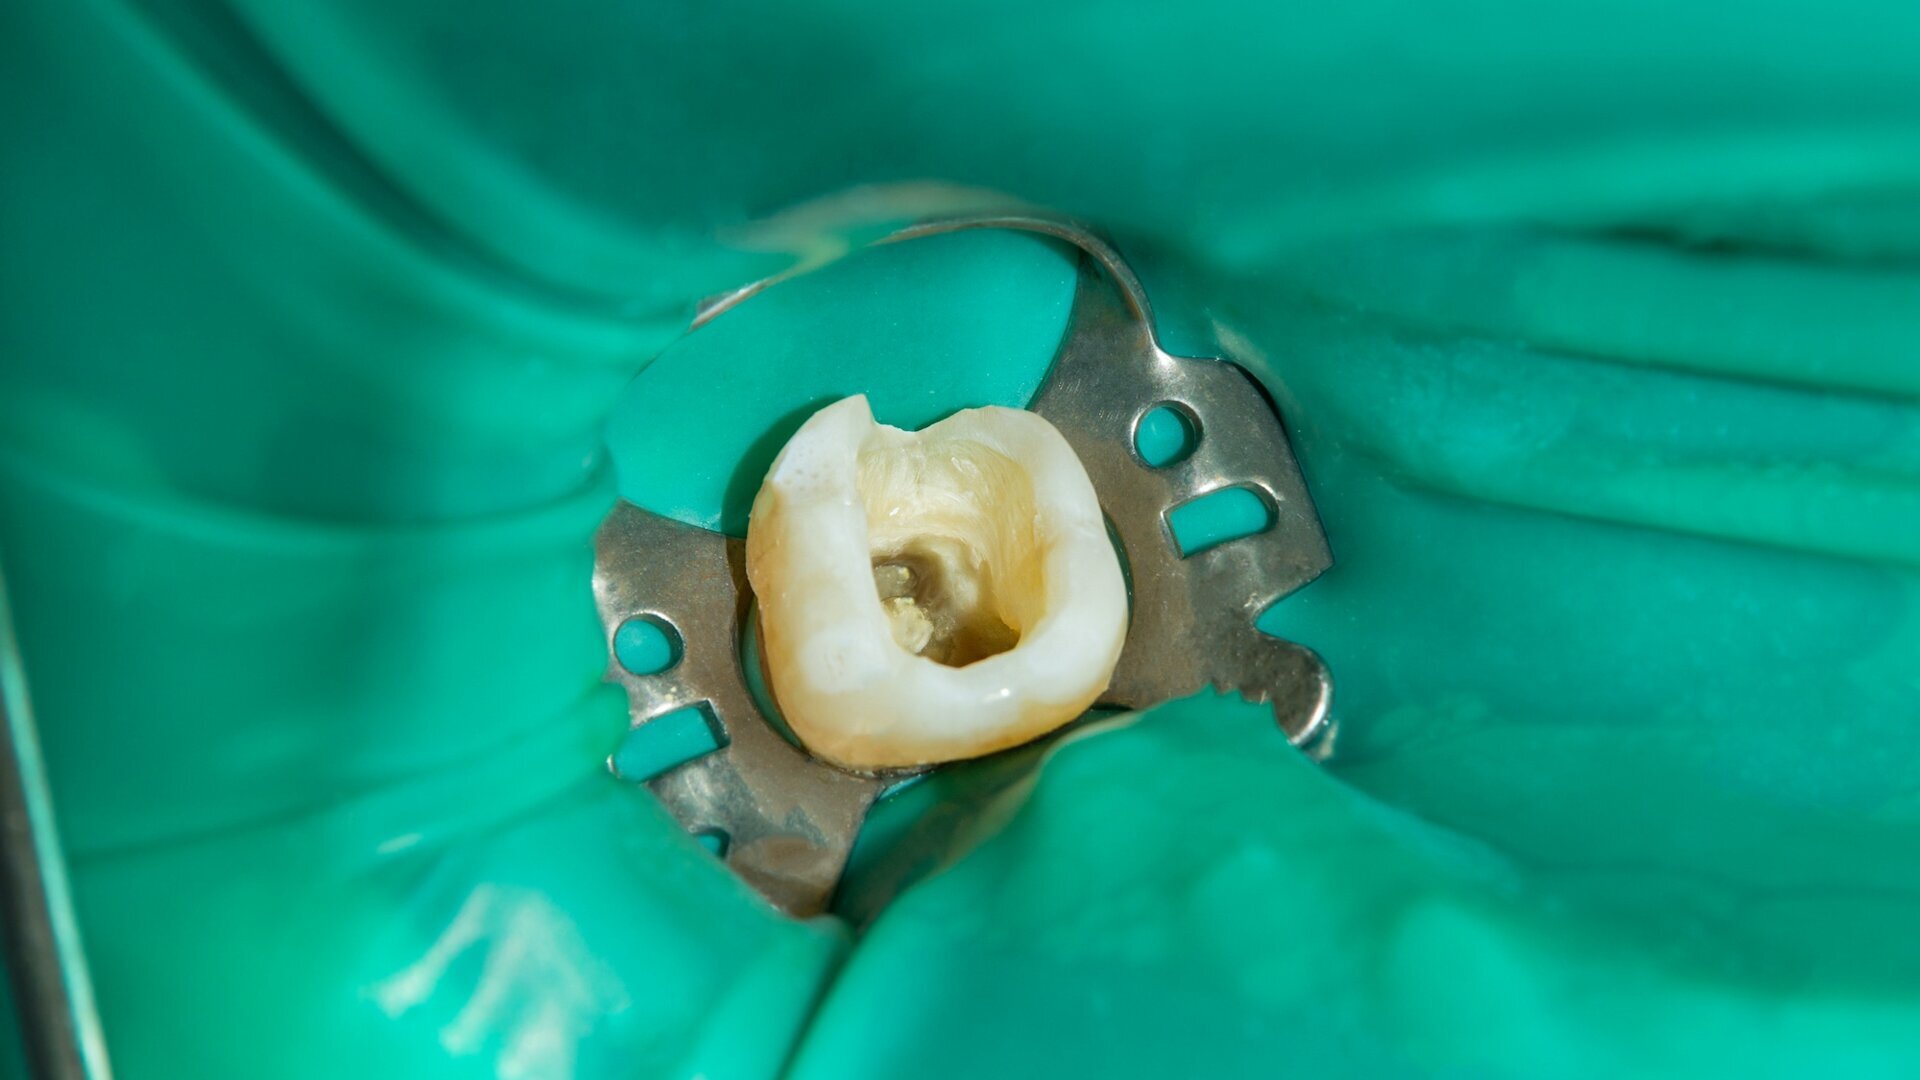

Dental dams are an essential tool when performing endodontic treatment. Their importance, however, is sometimes underestimated. (Image: Sergii Kuchugurnyi/Shutterstock)

LEIPZIG, Germany: The idea of using a sheet of rubber to create a dry work environment for dental professionals goes back to the nineteenth century and can be attributed to Dr Sanford Christie Barnum. In the spring of 1864, the dentist from New York had the idea of making a hole in his protective napkin and placing it around his patient’s tooth. And just like that, the rubber dam was born. Now, over 150 years later, the use of rubber dams during endodontic procedures is considered common practice and is recommended by international associations and organisations. However, for various reasons, not all dental professionals performing endodontic treatment adhere to these standards. General dental practitioners seem to struggle with its use more than endodontists do. But why is this the case and what can be done to promote rubber dam tooth isolation?